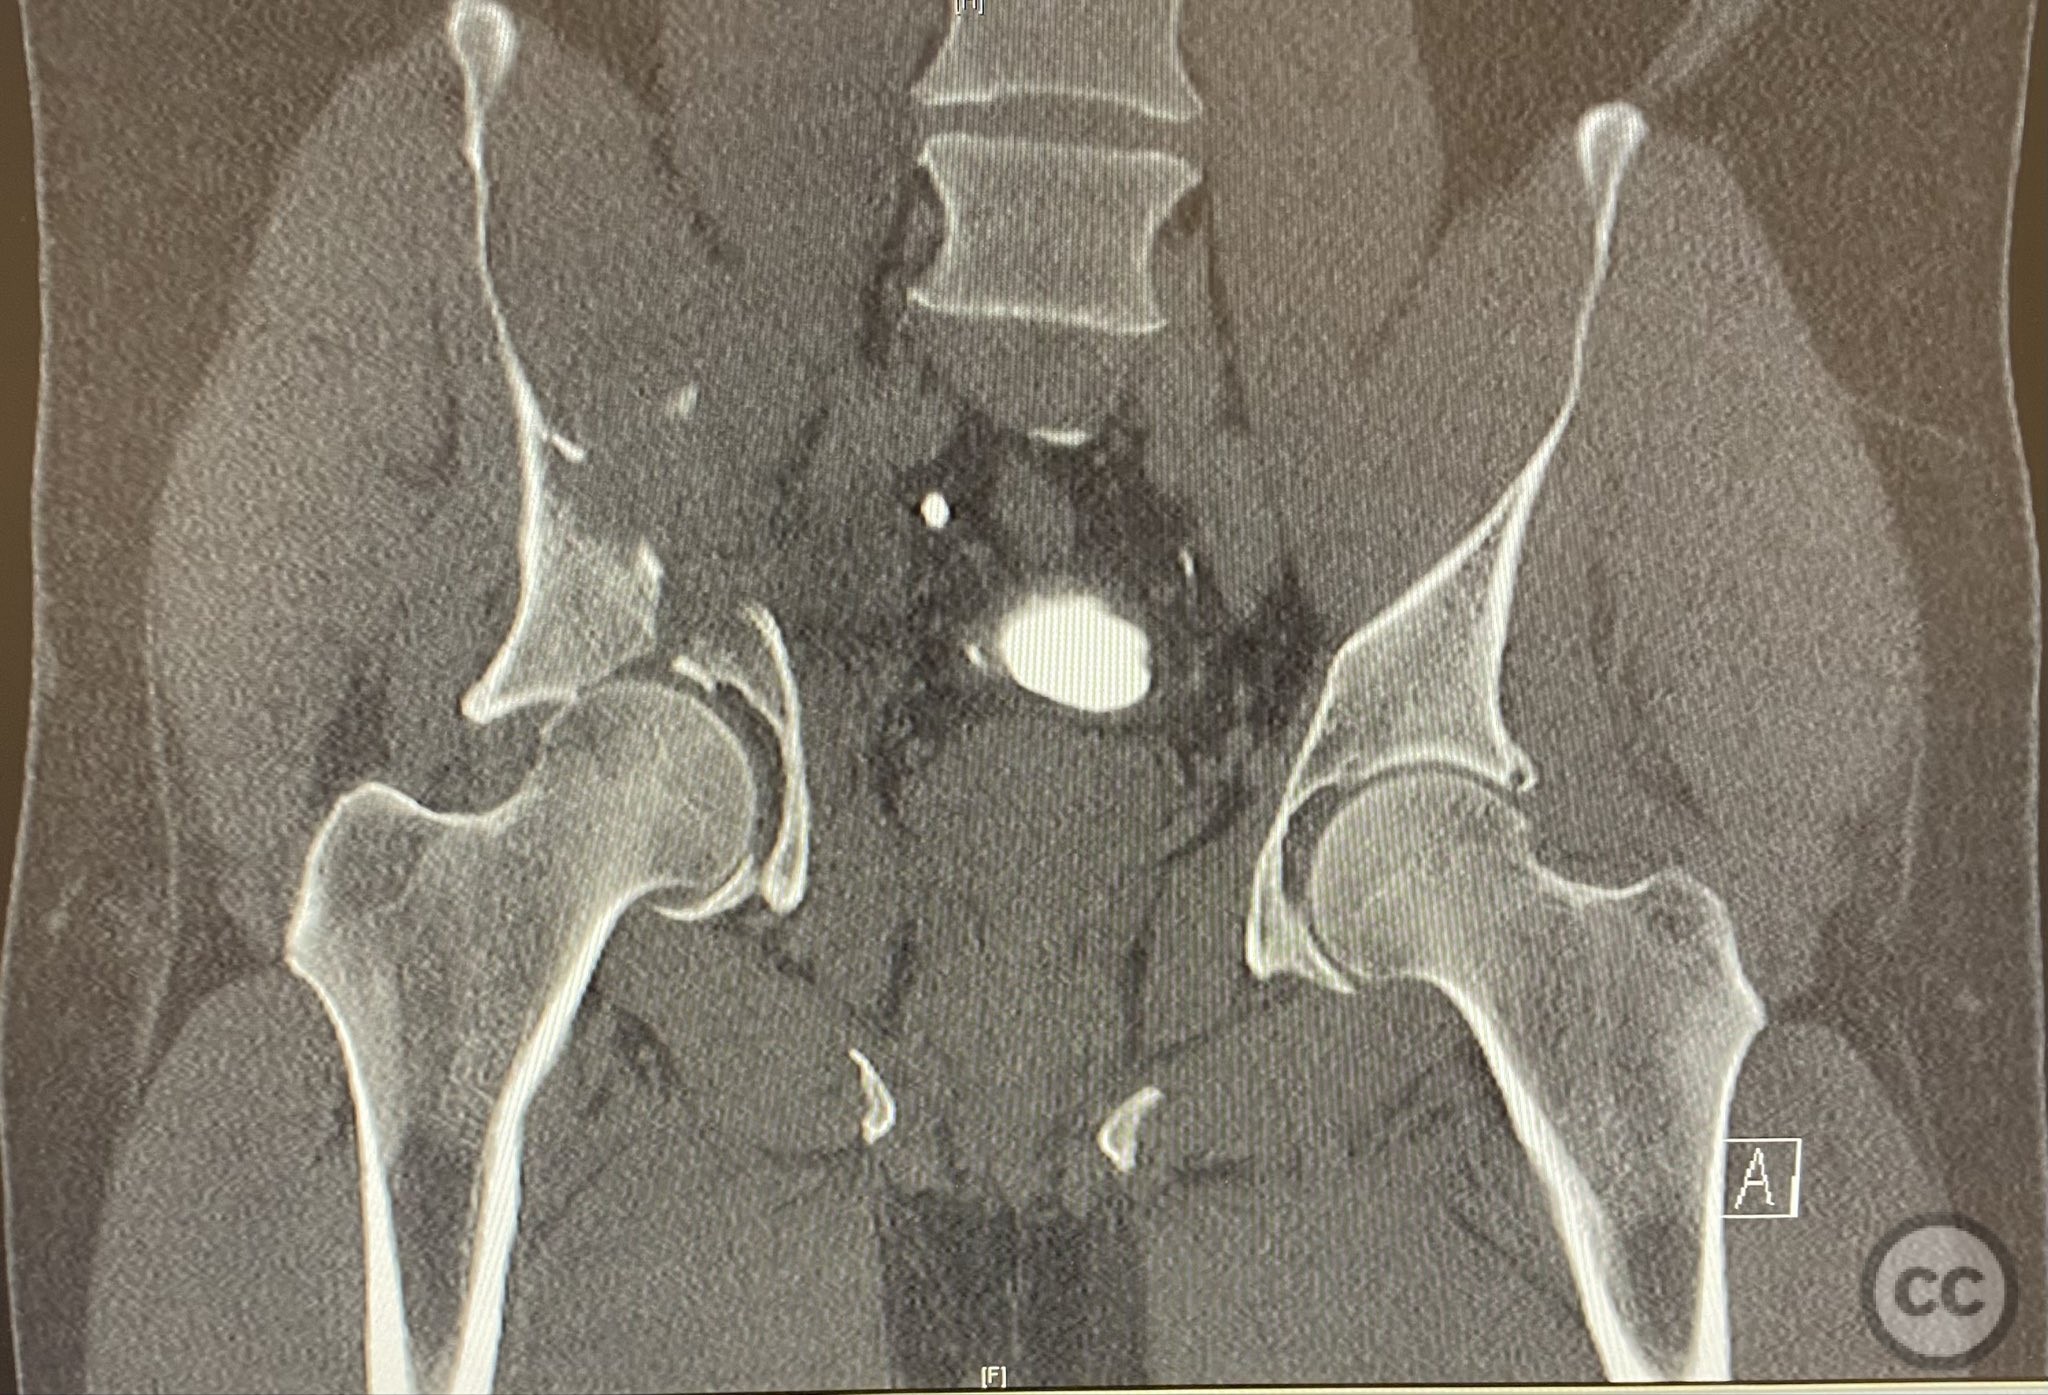

Clinical and radiological findings:  A patient presented with a combined anterior column and posterior hemi-transverse (AC/PHTr) acetabular fracture. Plain radiographs demonstrated multiple displaced fragments involving the acetabular dome and femoral head region, with clear disruption of the anterior column and posterior transverse components. Advanced imaging, including axial and coronal CT, provided detailed visualization of cortical surface displacement, fragment orientation, and associated soft tissue status. The edge of the intact dome and femoral head injuries were identified, as well as a residual defect at the edge of the dome following reduction. AO/OTA classification: 62B2 (anterior column with posterior hemitransverse).

Surface renderings from preoperative imaging facilitated intraoperative correlation between radiographic and fluoroscopic views, aiding in precise interpretation of fragment orientation during reduction. The use of focal plates allowed for maintenance of provisional reductions with bone holding clamps during definitive fixation. Restoration of radiographic lines was confirmed on intraoperative AP fluoroscopy, while postoperative axial CT demonstrated successful central dome repair with a residual edge crush defect at the dome margin.